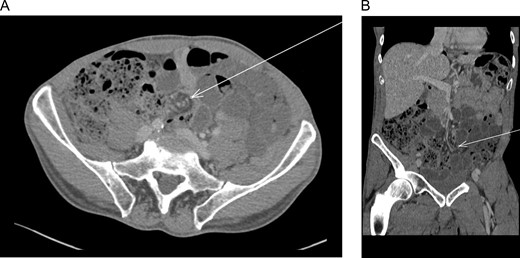

An abdominal computerized tomography (CT) demonstrated SBO with suspected volvulus (Fig. 1).

(A) Abdominal computed tomography (axial) revealed dilation of small intestine with a rotation of the mesentery around the mesenteric vessels (whirl sign) (arrow). (B) Abdominal computed tomography (coronal) revealed dilation of small intestine with a rotation of the mesentery around the mesenteric vessels (whirl sign) (arrow).